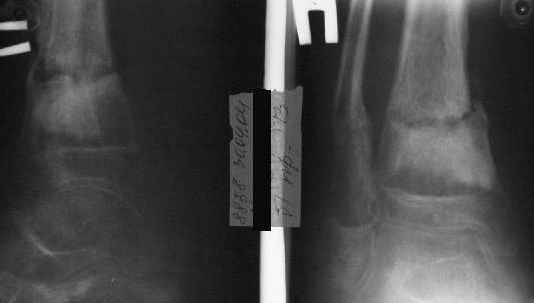

Фиксация

|

в гипсе

A> В январе 2005: варусная деформация н\3 голени,

А на вытяжении и в гипсповязке в течение 4 мес варуса видно не было?

Чего было ждать?

Деформация появилась и наростала во времени при фиксации в гипсовых повязках.